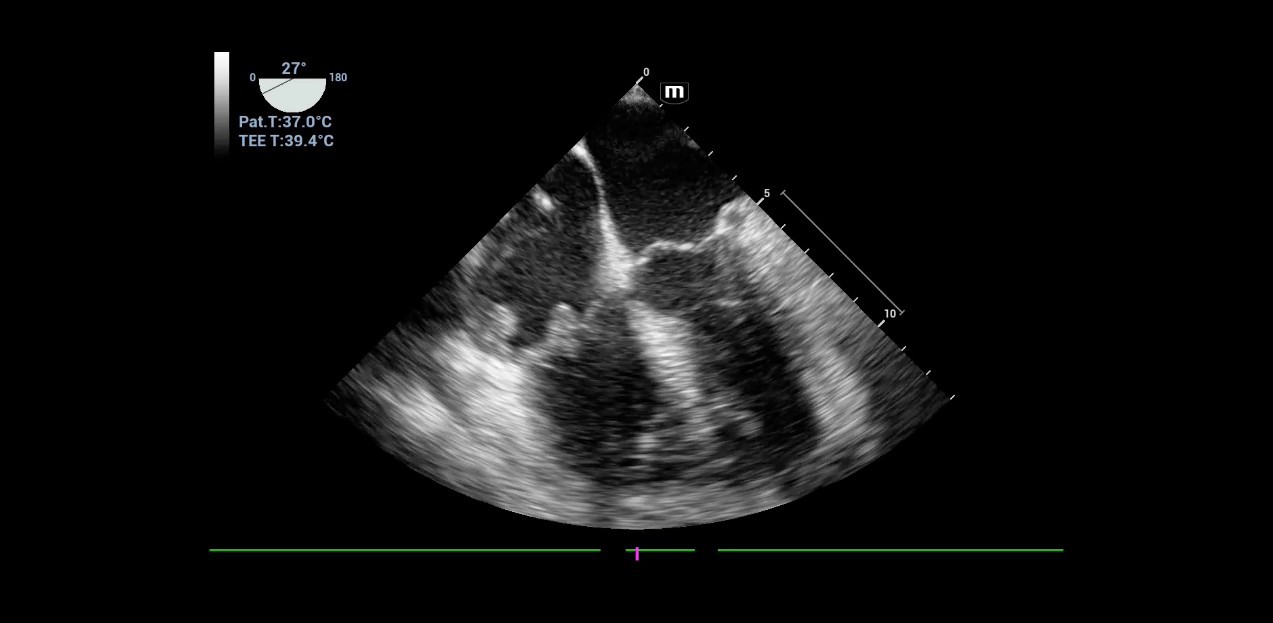

7. Patient with pacemaker and unclear sepsis. The image (TEE examination) clearly shows deposits on the tricuspid valve. Vegetations on the pacemaker cable are also found in the dynamic examination.